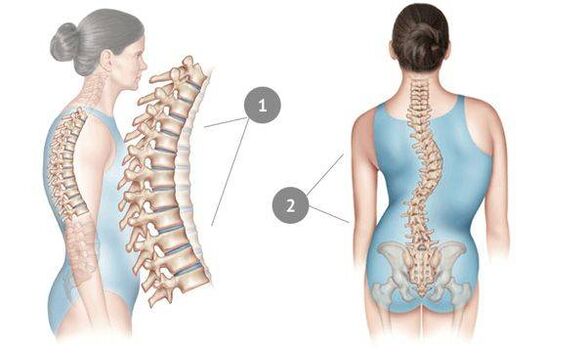

ကျောရိုး၏အဆင့်မြင့် osteochondrosis ကို scoliosis တွင်ဖော်ပြသည်။ တခါတရံတွင် ရောဂါသည် သားအိမ်ခေါင်း ကျောရိုးသို့ ပျံ့နှံ့သွားပြီး အသံဆုံးရှုံးမှုကို ဖြစ်စေသည်။